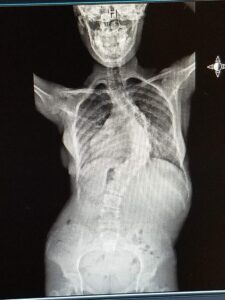

In June 2018, I was diagnosed with 60-degree scoliosis. The curvature threatened my heart and lungs. I wore a brace to slow its progression, but the curve worsened, making surgery unavoidable.

Despite the emotional weight, I faced spinal fusion surgery with determination. Surgeons placed 28 screws and two rods in my back. It was life-altering, but it gave me stability and protected my heart and lungs. I’m so grateful for Dr. John Ashgar and the amazing work he did.